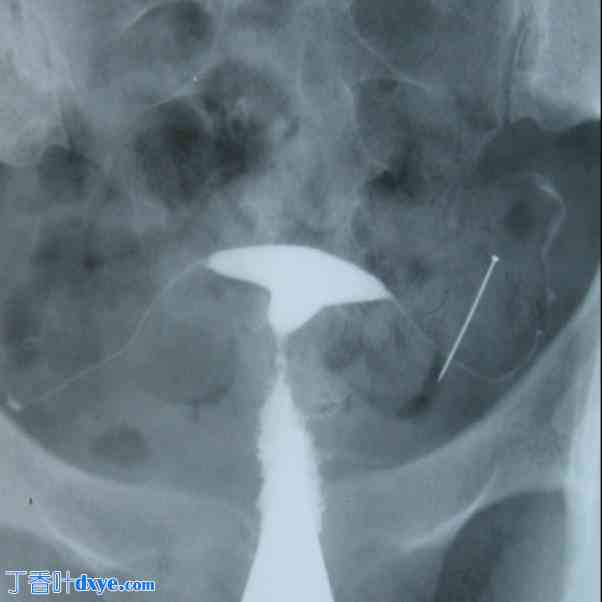

图 3。

A) 注射造影剂后,子宫输卵管造影仅显示宫颈不透明。由于晚期结核感染,子宫和输卵管钙化。钙化淋巴结也很明显。补充检查证实为生殖器结核。B) 宫腔正常。可见双侧输卵管峡部中段阻塞。未检测到腹膜溢出。骨盆左侧的圆形钙化区域表示由生殖器结核引起的卵巢钙化。